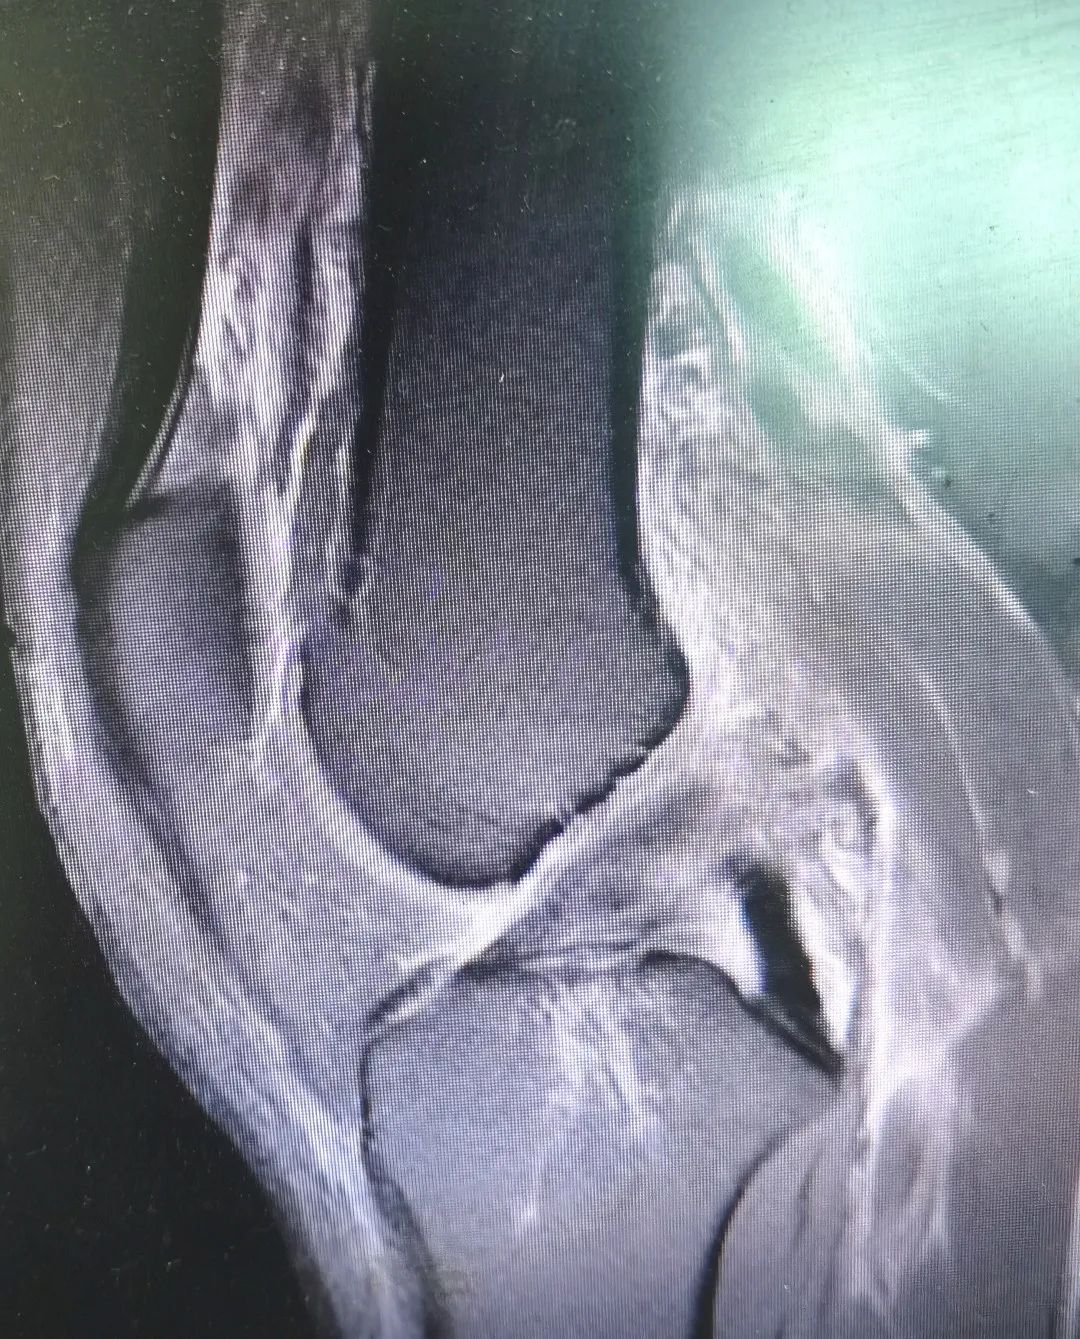

患者受伤部位肿胀畸形,已经严重到无法行走的程度,骨科医师经过仔细体查并结合辅助检查结果,诊断陈先生为 “1、左膝关节多发韧带损伤:前交叉韧带断裂,后交叉韧带断裂;2.后外侧复合体损伤:外侧副韧带损伤,腓肠肌外侧头止点损伤,股二头肌止点损伤,关节囊撕裂;3、腓总神经损伤”,建议行手术治疗,陈先生及家属表示理解并同意手术。

手术当天,麻醉医师给患者进行“腰硬联合麻醉”后,医院骨伤关节科团队邹晖主任带领袁雄、杨奇、罗毅医师一起在陈先生的左膝关节前内侧和前外侧入路各开一0.8厘米入口直达关节腔,在关节镜下一期重建了前交叉韧带、后交叉韧带,修复了外侧副韧带、腓肠肌外侧头止点、股二头肌止点,修复了关节囊,同时探查了腓总神经,整个复杂的手术过程一气呵成。目前,患者病情正在恢复中,患者主管医师预计手术6周后,陈先生可以进行日常活动。